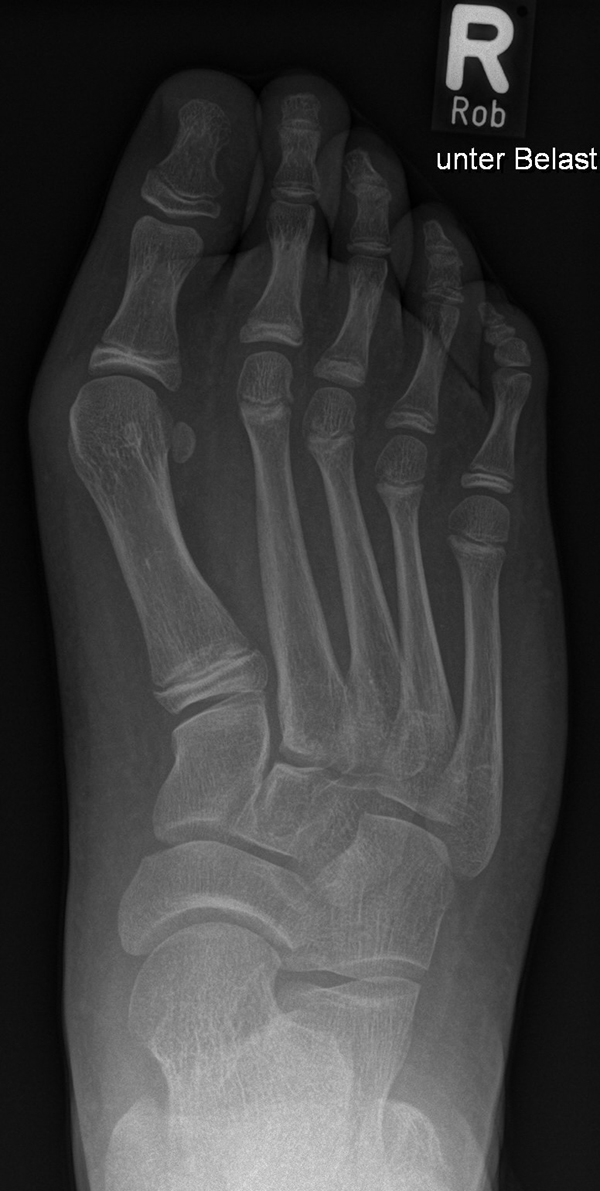

Diagnostisches Vorgehen

Damit die minimalinvasive Fußchirurgie zur Korrektur kindlicher oder jugendlicher Fußdeformitäten erfolgreich angewendet werden kann, erfordert die präoperative Diagnostik Röntgenbilder in drei Ebenen am stehenden Fuß. Röntgenbilder ohne Belastung des Fußes sind nicht zielführend. Im Fall von schweren Rückfußdeformitäten wird das obere Sprunggelenk in die radiologische Diagnostik mit einbezogen in Kombination mit der Rückfußaufnahme unter Belastung („Saltzman View“). Das OSG wird in zwei Ebenen geröntgt. Die streng seitliche Aufnahme des OSG kann bei den komplexen Fußdeformitäten mit der seitlichen Aufnahme des Fußes unter Belastung kombiniert werden. Das reduziert die diagnostische Strahlenbelastung der Kinder.

Indikationen für die beschriebenen Röntgenaufnahmen sind Klumpfußdeformitäten zur Beurteilung eines „flat top talus“ oder neurologische Grunderkrankungen mit varischer Fersenstellung wie zum Beispiel bei HSMN (Hereditäre Sensorische Motorische Neuropathie).